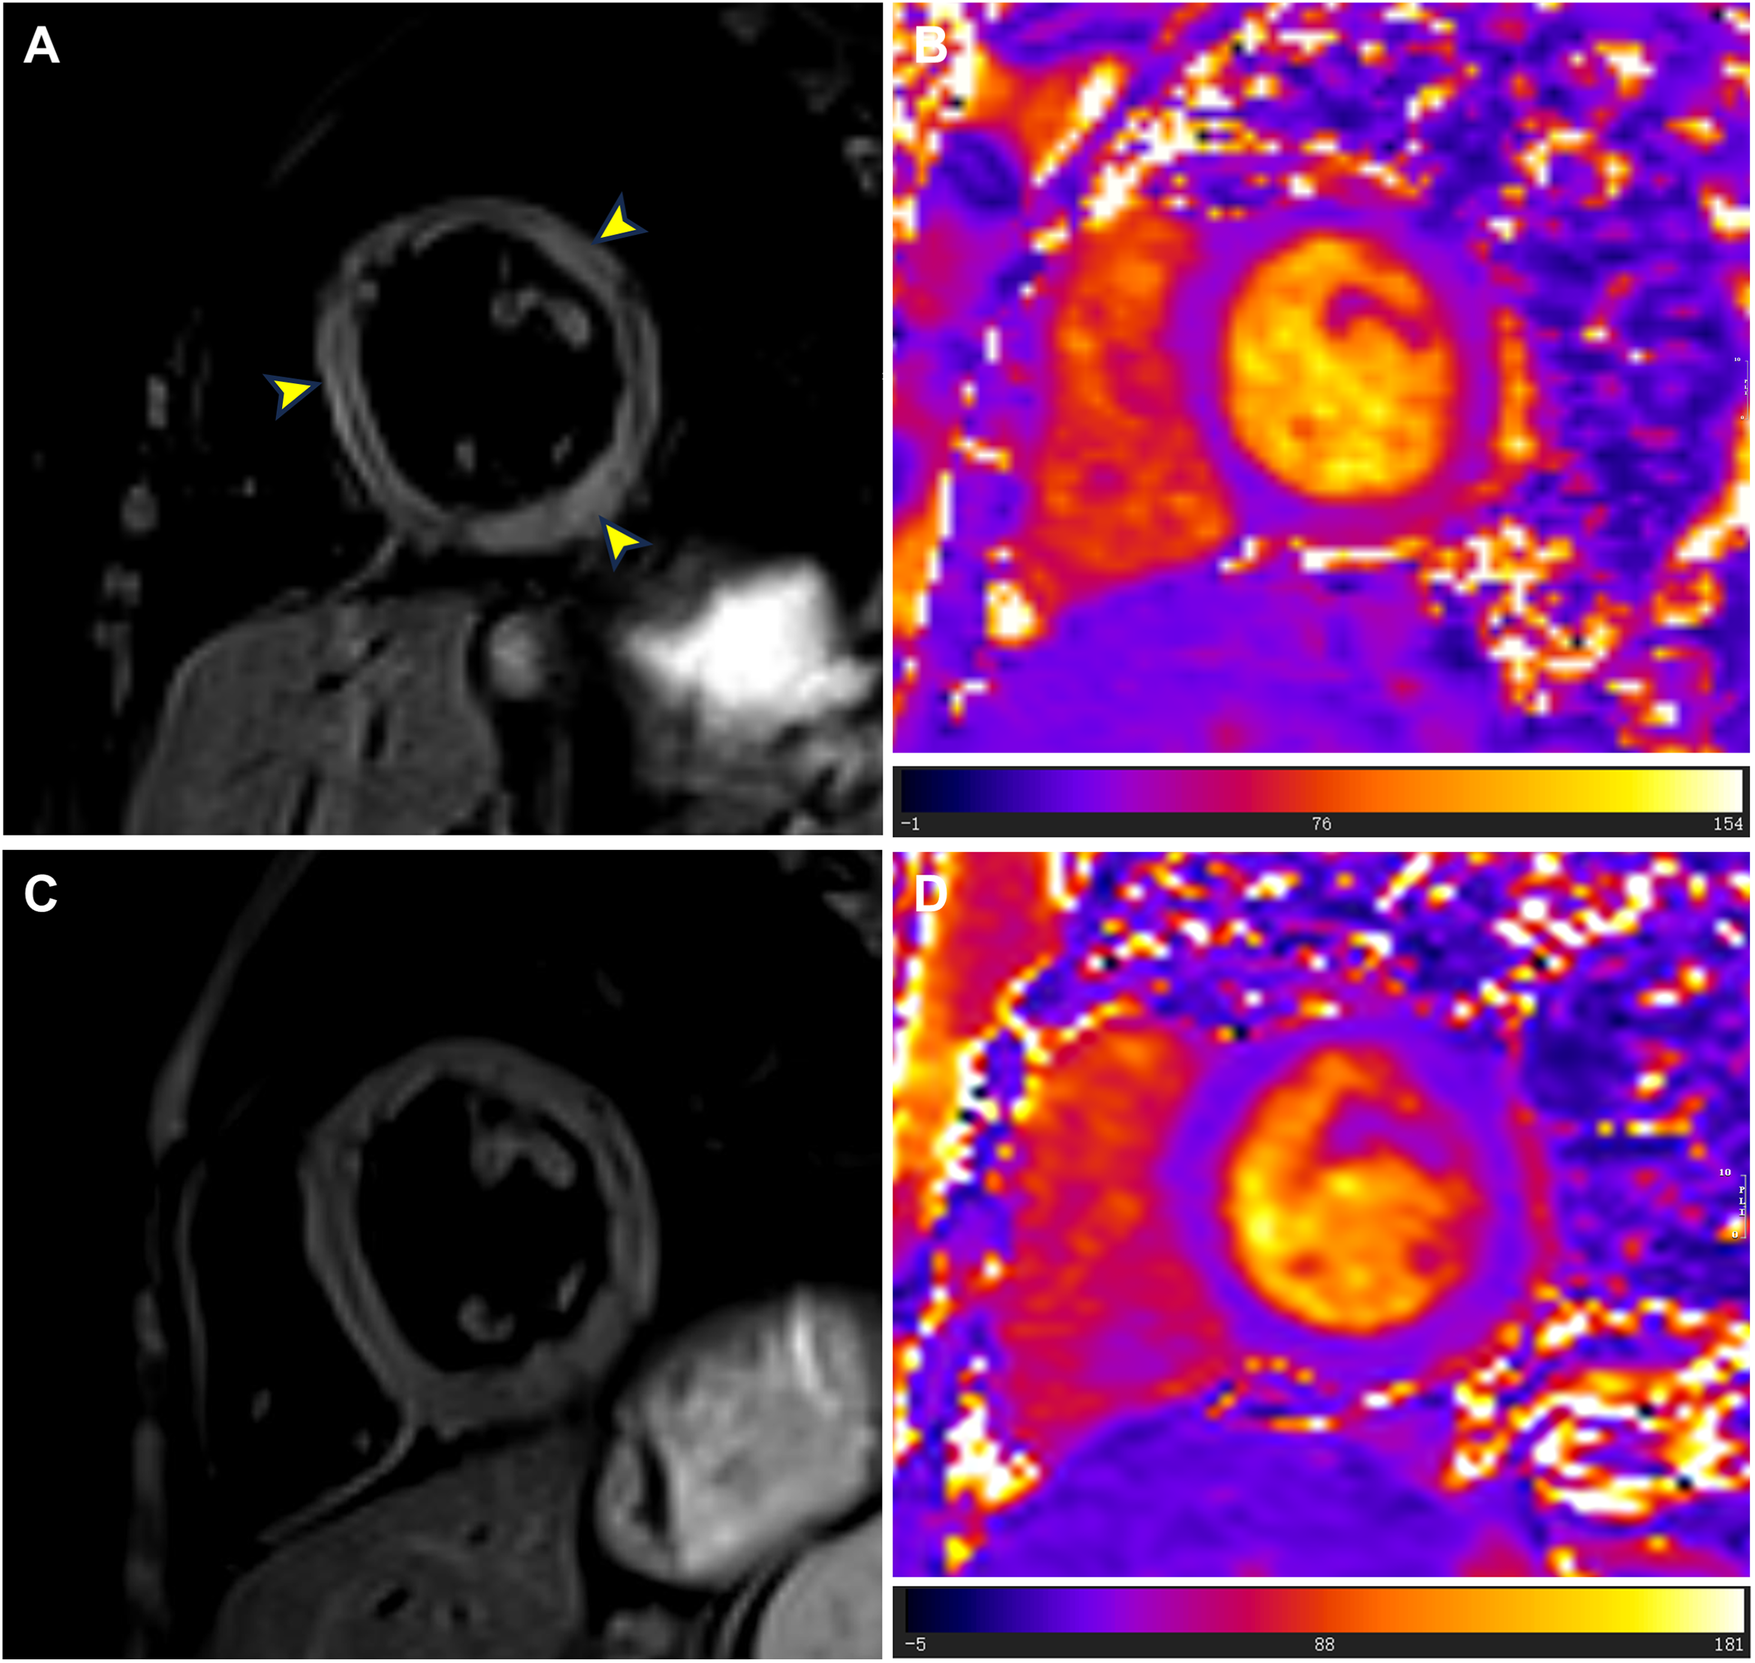

Figure 3

T2-weighted imaging and T2 mapping images at admission and follow-up. (A) At admission, T2-weighted imaging showed localized high signals in the left ventricular septum, lateral wall, and inferior wall (yellow arrowheads). (B) At admission, T2 mapping images showed abnormally elevated T2 values (mean value = 56.9 ms) in the basal to middle segments of the interventricular septum and inferolateral walls. (C) During the follow-up cardiac magnetic resonance examination in July 2024, T2-weighted imaging showed no signs of myocardial edema. (D) During the follow-up cardiac magnetic resonance examination in July 2024, T2 mapping images showed reduced T2 values (mean value = 42.0 ms) in the basal to middle septal and inferolateral walls.

Although the patient did not report any cardiac symptoms, the elevated cTnI levels and abnormal ECG findings indicated possible myocardial necrosis. Thus, a CMR examination was recommended. CMR showed inflammatory myocardial edema with localized T2 hyperintensity (T2 ratio, 2.4; T2 mapping, 56.9 ± 0.4 ms) in the inferolateral walls and interventricular septum from the basal to middle segments (Figures 3A,B). Additionally, LGE progression in the inferolateral walls and interventricular septum was observed, supporting a diagnosis of acute myocarditis (Figures 1E,F).

The patient was treated with intravenous immunoglobulin (20 g daily, administered over a 4-h infusion period each day) for 2 days. Because the patient developed hypokalemia on the day after he had been diagnosed with acute myocarditis, we administered a combination of oral prednisolone acetate (60 mg daily), enalapril (10 mg daily), metoprolol (50 mg daily), potassium chloride sustained-release tablets (1 g daily), and broad-spectrum antibiotics for 7 days. After this treatment, the patient's symptoms improved and his cTnI levels gradually decreased, leading to hospital discharge. Approximately 1 month later, non-contrast CMR showed a clinically significant reduction in myocardial edema (T2 ratio, 1.8; T2 mapping, 42.2 ± 1.7 ms), along with a cTnI level of 0.14 μg/L. An outpatient follow-up examination after about 110 days revealed that the patient's cTnI levels had returned to baseline (Figure 4A). After improvement of myocarditis, an ECG showed abnormal Q waves and T-wave changes in leads II, III, and aVF (Figure 2B). Follow-up echocardiography findings were normal. In July 2024, enhanced CMR showed no signs of myocardial edema (T2 ratio, 1.7; T2 mapping, 42.0 ± 0.9 ms) (Figures 3C,D) but revealed an increased range of LGE in the lateral walls of the basal segment (Figures 1G,H). The patient is currently asymptomatic and continues to undergo monitoring via outpatient and telephone follow-up. The patient's timeline is summarized in Figure 4B. Written informed consent was obtained from the patient for publication of potentially identifiable images or data included in this article.